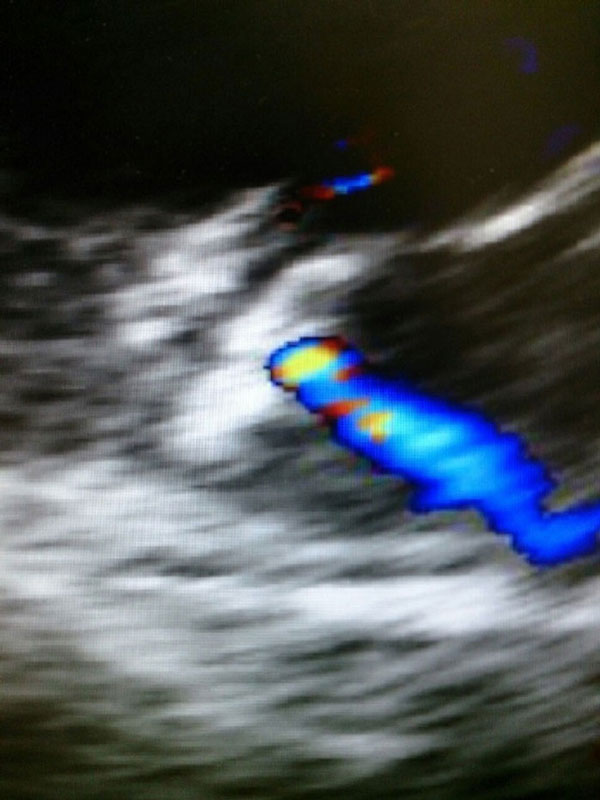

(Նկար 2) Պրոթեզի իմպլանտավորումից անմիջապես հետո, գունավոր դոպլեր սկանավորման ժամանակ պարզ երեվում է միջնախասրտային շունտը: